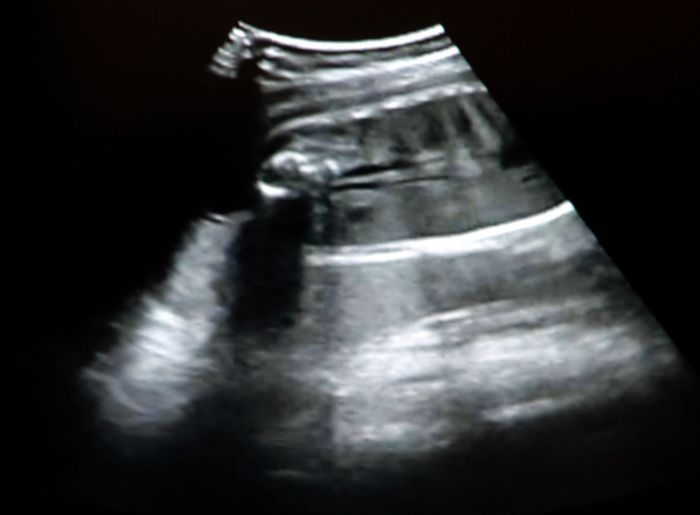

Ahojky Milu, omlouvám se minule jsem Ti přehodila ve jméně písmenka

a dnes mi konečně manža rozchodil kopírku, tak tadyk je slibovanej obrázek snad bude vidět dobře, optruj se zatím ahojky

no když na to koukám a srovnám,tak jsem si jistá že to bude klučina

moc ti děkuji za obrázek...jsi moc hodná